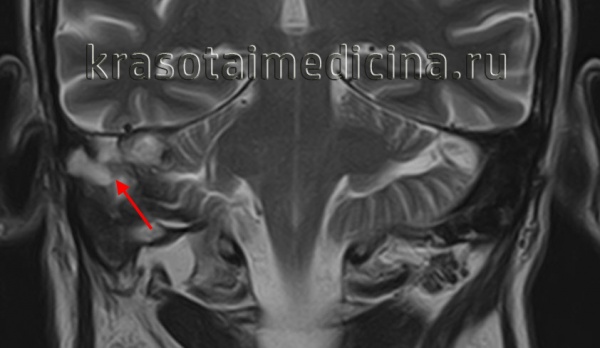

МРТ головы. Гиперинтенсивный сигнал в области сосцевидной пещеры, сосцевидного отростка и пирамиды правой височной кости (холестеатома)